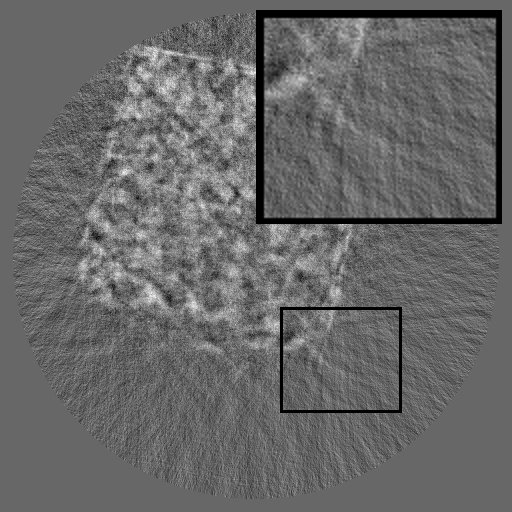

As shown in Fig 2, HRSino builds upon RePaint (Lugmayr et al., 2022) as its default backbone and restructures the inference process into a three-stage resolution-guided pipeline. The sinogram is first denoised at low resolution to establish global structure, then refined at mid resolution, and finally completed at full resolution through patch-wise inference. At each stage, the upsampled output from the previous resolution is fused with the current input before denoising, ensuring hierarchical guidance across scales. This hierarchical design avoids full-frame activation and substantially reduces memory usage while preserving long-range consistency. To further improve efficiency under the structural characteristics of sinograms, HRSino introduces two inference-time modules: (1) frequency-aware patch skipping, which exploits the spectral sparsity of background regions to bypass redundant computation, and (2) structure-adaptive step allocation, which leverages local structural heterogeneity to adjust denoising depth per patch.

Refer to caption

Figure 2: Overview of HRSino. The left illustrates the three-stage resolution-guided pipeline: low resolution followed by mid and high resolutions in a progressive refinement scheme, with the final stage performed patch-wise for detail recovery. At each stage, the upsampled output from the previous resolution is fused with the current input before denoising. The right zooms into the high-resolution stage, where two modules are applied: frequency-aware patch skipping (bypassing low-information patches) and structure-adaptive step allocation (assigning variable denoising steps by patch complexity).